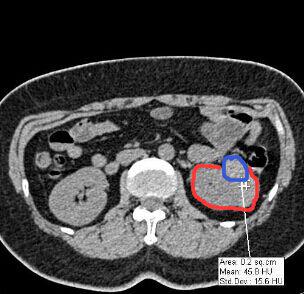

相信很多人和筆者一樣,還是感到疑惑,傳統(tǒng)拍片和3D打印出來的器官模型具體有哪些不同,后者又如何表示病變或者需要進行手術(shù)的位置呢?對于這一點,專業(yè)進行3D設(shè)計和打印的東莞創(chuàng)客聯(lián)盟公司給讀者解答了這個疑惑。其負(fù)責(zé)人陳小姐表示,通過不同顏色來表達病變或需要進行手術(shù)的位置,所打印出器官模型足以讓病變位置一目了然。為便于說明,其負(fù)責(zé)人展示他們做的一個案例:

某醫(yī)院的外科醫(yī)生需要做一個3D腎臟模型,但CT片拍出的二維圖像中,其腫瘤位置只是通過灰色的色階來表示(臨床應(yīng)用中稱之為CT值),如上圖中紅色圈出來的是腎臟截面,藍(lán)色則為腫瘤位置。從圖中可以看出,在CT片子中藍(lán)色部分僅僅比紅色部分要白一點。